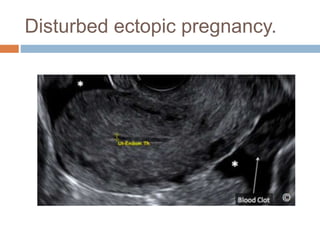

Ectopic pregnancy

Disturbed ectopic pregnancy.